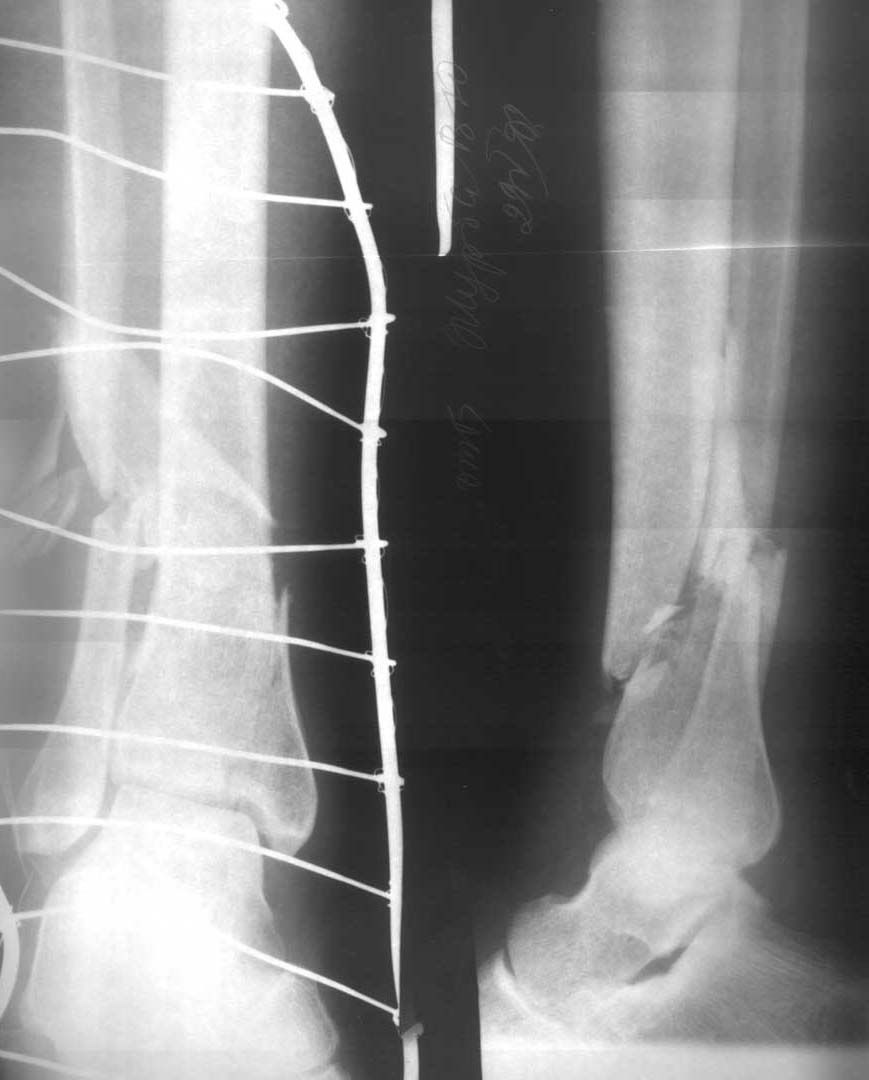

Мужчина, 35 лет. Травма в угольной шахте. Сотрясение головного мозга, вторично открытый оскольчатый перелом обеих костей правой голени. Две раны по наружной поверхности размерами до 1 см. Тактика лечения?С уважением,А.В.ВладзимирскийДонецкий НИИ травматологии и ортопедии

• Кликните для загрузки файла 2905.jpg

1.Закрытый интрамедуллярный остеосинтез с предварительной фиксацией дистального эпиметафиза спицами, и после введения стержня - винтами.

или

2.Остеосинтез спице-стержневым аппаратом любой компоновки, с которой чувствуете себя уверенно - чисто кольцевой или гибридный.

"Я бы использовал пластину для фиксации перелома. На мой взгляд, он расположен слишком низко, чтобы использовать винт. Как альтернативу можно использовать управляемую внешнюю фиксацию. Рана в сантиметр и состояние кожи при определенном лечении антибиотиками не будут представлять проблему при внутренней фиксации. Может быть, вы сможете предоставить более полную информацию о состоянии кожи"

На мой взгляд, в данной ситуации показан остеосинтез спице-стрежневым АВФ на 3 кольцах с минимумом чрезкостных элементов. После заживления ран можно усилить аппарат. С уважением,Д.панчуков, Ангарск, БСМП.